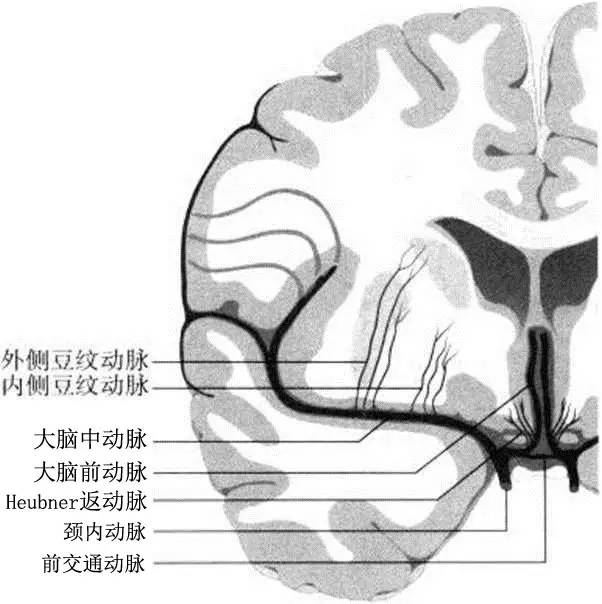

由高血压引起的脂质透明样变性和中膜过度增生主要累及:①大脑中动脉的豆纹动脉穿通支(图2);②大脑前动脉的穿支,通常指Heubner动脉(图3和图4);③前交通动脉发出的穿通支(图5和图3);④大脑后动脉发出的丘脑穿通动脉和丘脑膝状体穿支(图3);⑤由基底动脉发出,到达脑桥、中脑和丘脑的旁中央穿通支。在某些情况下,母动脉粥样硬化斑块形成或穿支口微小粥样硬化斑块会堵塞穿通动脉(图6)。动脉粥样硬化性穿支闭塞的累及部位与脂质透明样变性有相同之处,但同时前者还可累及较大的动脉(例如颈内动脉的分支脉络膜前动脉以及大脑后动脉发出的丘脑膝状体动脉)。

图3 基底节和丘脑的穿通动脉